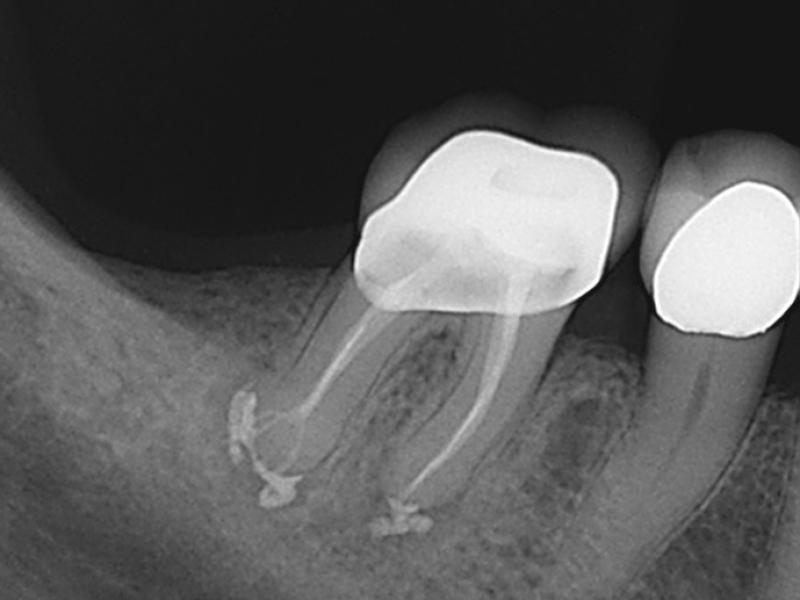

Calcified Canals with Healing Evidence

Pre-Op